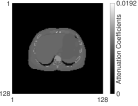

We used the XCAT [44] phantom (Fig. 2) to simulate Y-90 PET following radioembolization. We set the image size to 128128100 with a voxel size 4.04.04.0 (mm3) and chose 100 slices ranging from lung to liver. To simulate extremely low count scans with high random fractions, typical for Y-90 PET, we set total true coincidences and random fractions based on numbers from patient PET imaging performed after radioembolization [45]. To test the generalization capability of the trained BCD-Net, we changed all imaging factors between training and testing dataset. Here, imaging factors include activity distribution (shape and size of tumor and liver background, concentration ratio between hot and warm region) and count-level (total true coincidences and random fraction). Fig. 2 and Table I provide details on how we changed the testing dataset from the training dataset. We trained BCD-Net using five pairs () of 3D true images and estimated images at each iteration (1 true image, 5 realizations). We generated multiple (5) realizations to train the denoising NN to deal with the Poisson noise. We also generated 5 realizations (1 true image, 5 realizations) as a testing dataset to evaluate the noise across realizations.

II-F Evaluation metrics

For the XCAT phantom simulation, we evaluated each reconstruction with contrast recovery (CR) (volume-of-interest (VOI): cold spot indicated in Fig. 2), noise across realizations, root mean squared error (RMSE), and contrast to noise ratio (CNR). For the physical phantom measurement, we used CR (VOI: hot spheres) and CNR averaged over multiple hot spheres. We define each VOI’s mask based on attenuation map interpolated to PET voxel size. For the patient measurement, we used CNR and the field of view (FOV) activity bias since the total activity in FOV is known (equal to the injected activity because the microspheres are trapped) wheareas the activity distribution is unknown:

where is mean counts in the VOI, is true ratio between hot and warm region, denotes the th voxel of an image , is the number of realizations ( in both XCAT phantom simulation and physical phantom measurement) and is the number of voxels in the volume of liver, is standard deviation between voxel values in uniform background liver (indicated in Fig. 2), and is the total number of voxels in the FOV. As the background region when calculating the patient CNR, we used a part of liver region that has relatively uniform activity distribution.

| Attenuation map (coronal) | Attenuation map (axial) | True activity (training) | True activity (testing) | Zoomed in |

|---|---|---|---|---|

![]() |